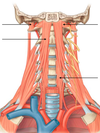

Vertebral compartment contents?

(4)

Vertebral compartment:

Cervical vertebrae

muscles

spinal cord

cranial nerves

visceral compartment contents?

(3)

Visceral compartment:

Larynx

pharynx

glands (thyroid, parathyroid, and thymus)

Vascular compartment contents?

(2)

Vascular compartments (2 of them):

Major blood vessels

CN X (vagus n.)